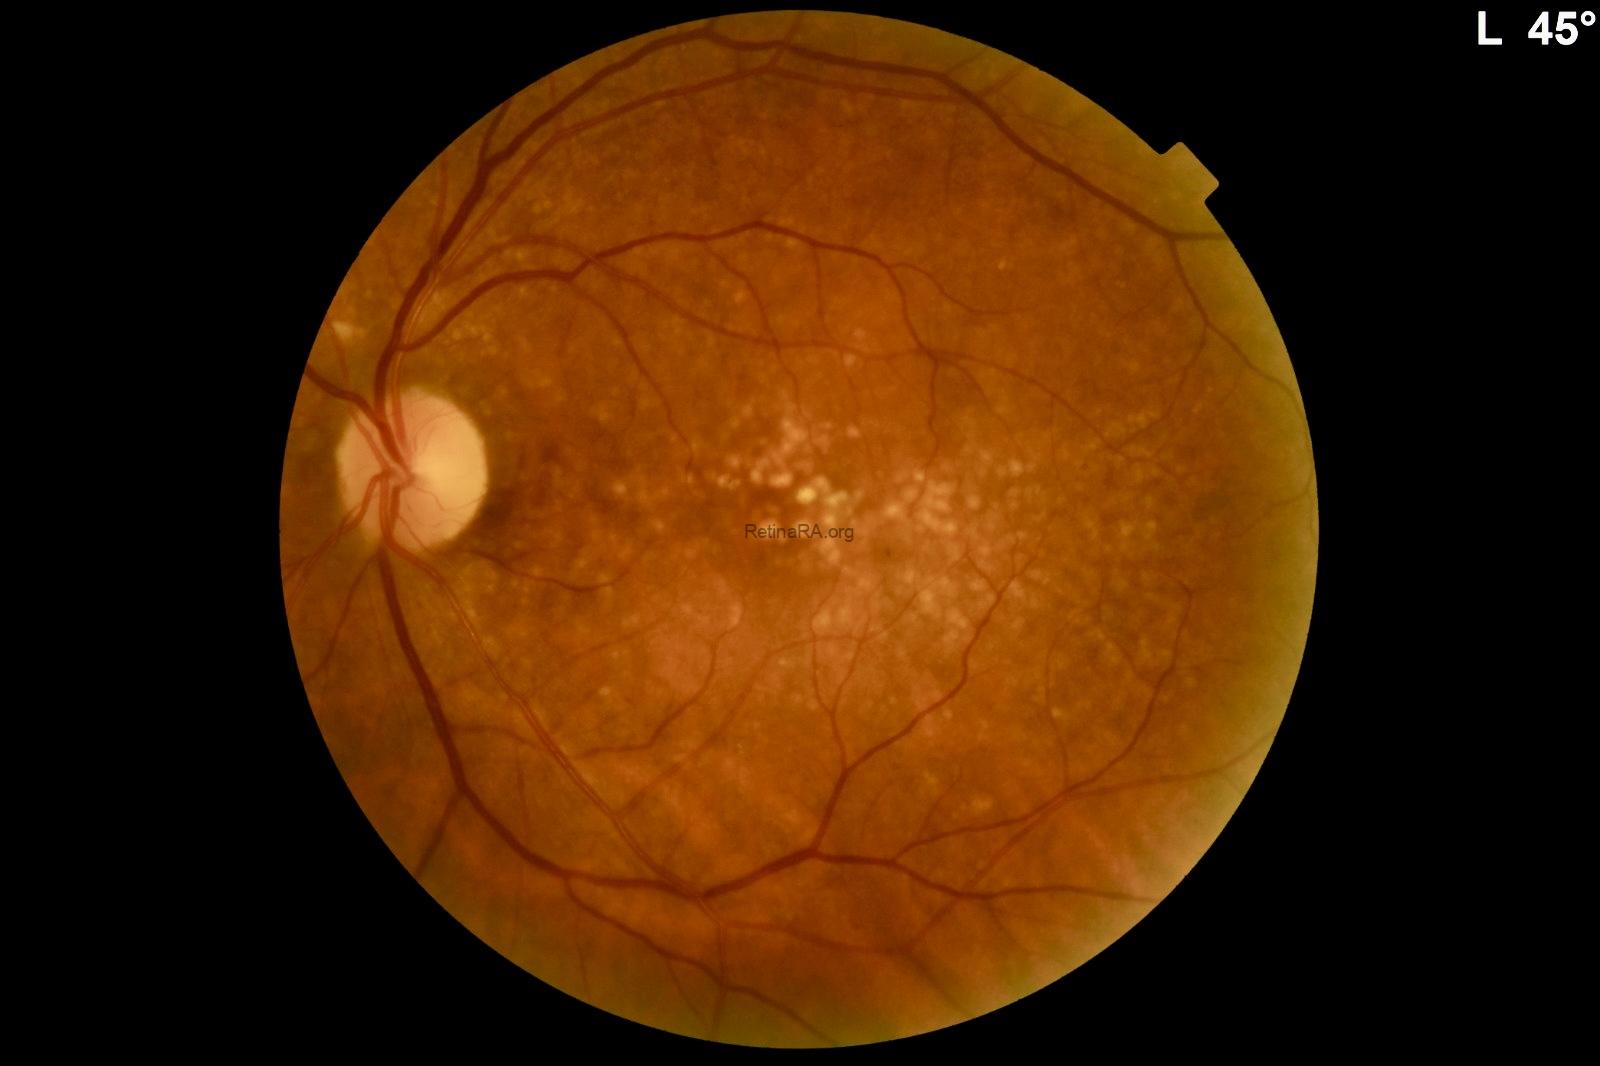

Gravitational tracks in chronic central serous chorioretinopathy: a multimodal imaging case

Patient history A 34-year-old male patient with a history of chronic central serous chorioretinopathy (CSC) [...]